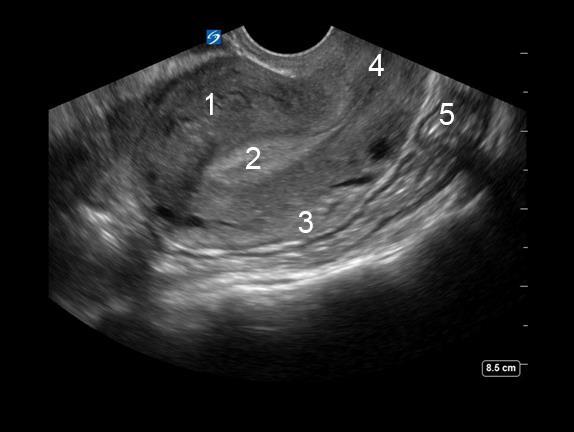

盆腔子宫图像

子宫

子宫内膜

宫颈

后盲囊